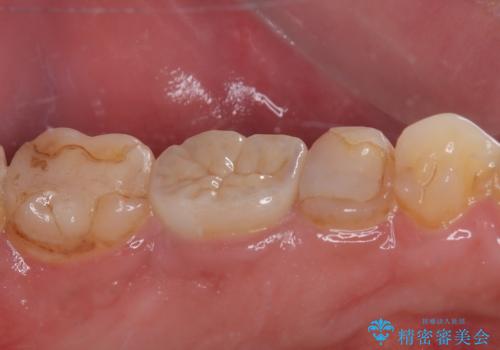

- 奥歯の歯肉から定期的に膿が出てくるとのことで来院された患者様です。

レントゲン写真などの診察を行った結果、根管治療が必要であったため、現在のクラウンを除去し、根管治療を行うこととしました。

根管治療後は症状を確認し、速やかにオールセラミッククラウンにて補綴治療を行うこととしました。